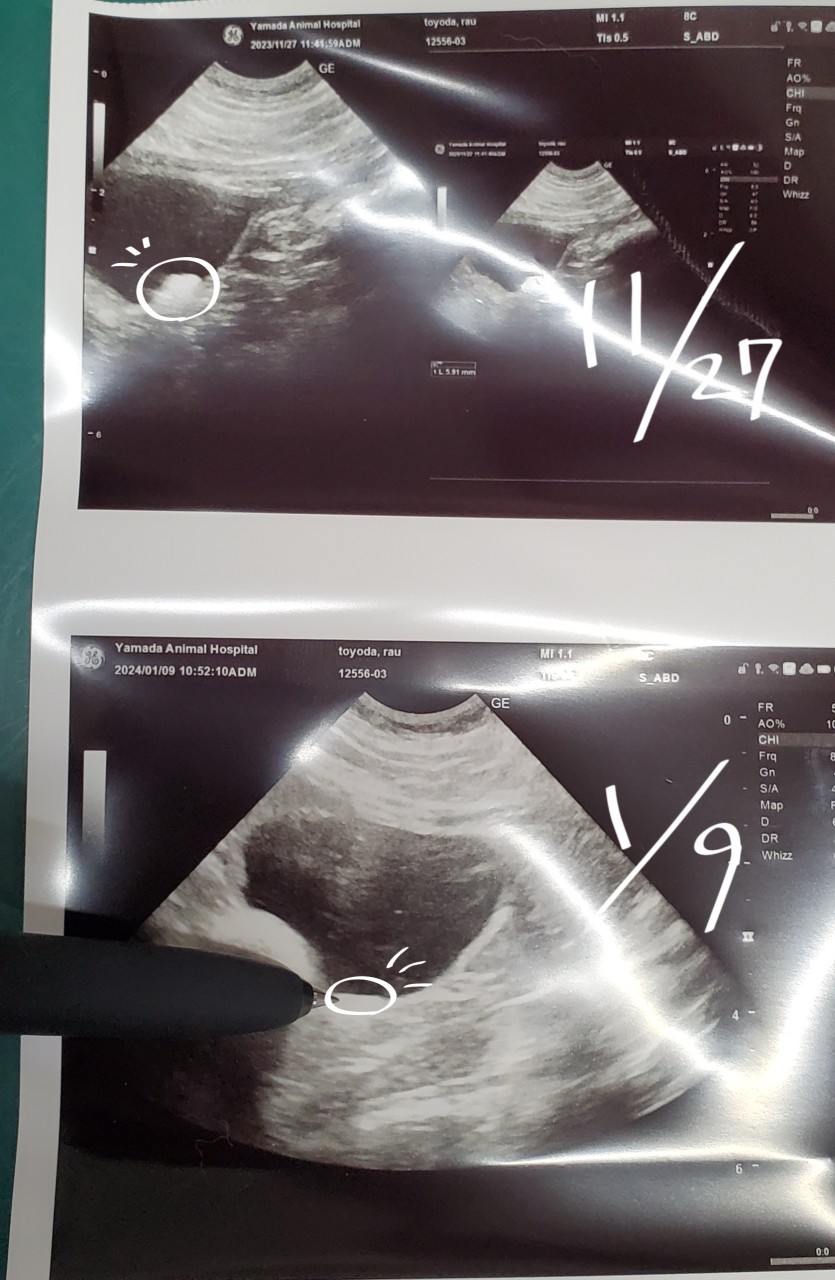

多発性だったから内臓が原発かもしれないって事で、今後定期的にエコー検査必須に。1/9にエコーしたら脾臓膵臓共に大丈夫でした。

1月にエコーしたらほぼ消えてた!!良かったーーーー!!!!!!!!!!!!!!!マジで良かった。もう何の病気にも掛からないでくれ……。

去年の11月に尿結石発症して、尿検査してもシュウ酸カルシウムなのかストルバイトなのか不明だったので、どちらにも効く『ヒルズ尿ケアC/D』を購入。